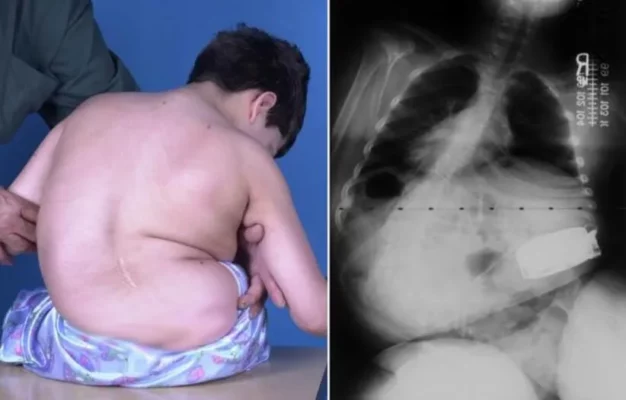

What is Considered Early Onset Scoliosis?

Early Onset Scoliosis Definition Understanding Early Onset Scoliosis Adolescent idiopathic scoliosis is typically diagnosed in [...]